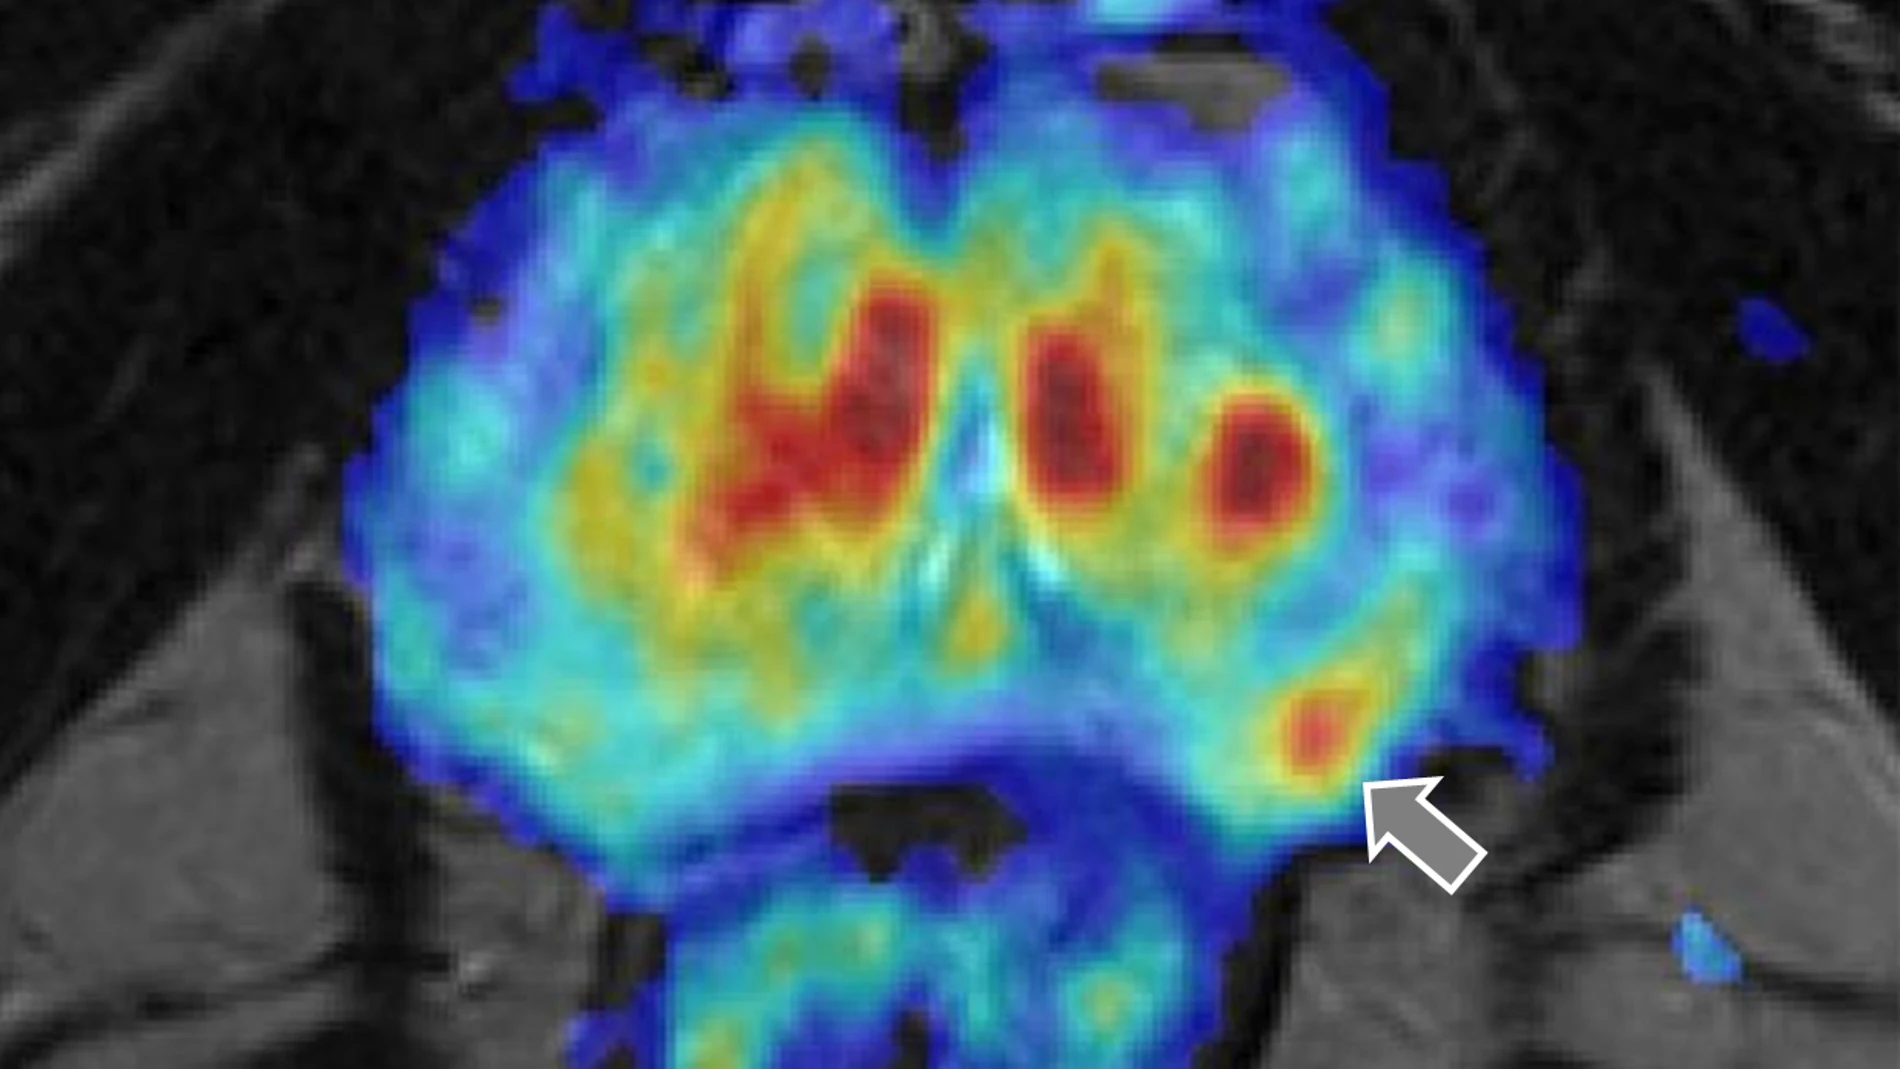

El papel del microbioma intestinal, es decir, las millones de bacterias que tenemos en el intestino, en la salud resulta cada vez más obvio. Ahora, investigadores de la Clínica Cleveland, en Estados Unidos, han demostrado por primera vez que las moléculas vinculadas a la dieta en el intestino están asociadas con el cáncer de próstata agresivo, lo que sugiere que las intervenciones dietéticas pueden ayudar a reducir el riesgo, según publicando en la revista «Cancer Epidemiology, Biomarkers & Prevention».

Este importante hallazgo se ha logrado a través del análisis de casi 700 pacientes y pueden tener implicaciones clínicas para el diagnóstico y la prevención del cáncer de próstata más letal. “Descubrimos que los hombres con niveles más altos de ciertas moléculas relacionadas con la dieta son más propensos a desarrollar un cáncer de próstata agresivo”, afirma la doctora Nima Sharifi, directora del Centro de Investigación de Enfermedades Genitourinarias de la Clínica Cleveland. “A medida que continuamos nuestra investigación en este campo, nuestra esperanza es que un día estas moléculas puedan utilizarse como biomarcadores tempranos del cáncer de próstata y ayuden a identificar a los pacientes que pueden modificar su riesgo de enfermedad haciendo cambios en la dieta y el estilo de vida”, añade.